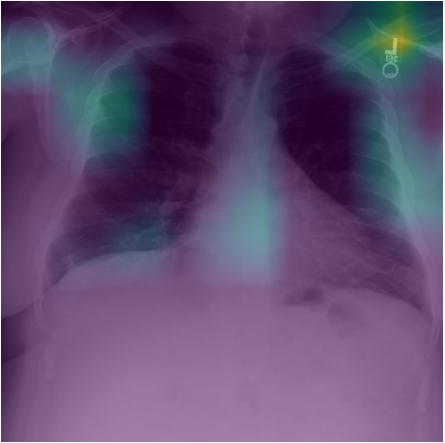

We measure our result both quantitatively and qualitatively. The qualitative result is shown in the Figure 5. Each row displays an example of a tuberculosis (TB) chest X-ray image taken from the validation subset of the TBX11k dataset. A detailed inspection of these images reveals a significant difference in how the teacher and student models attend to the visual features. Specifically, the teacher model tends to highlight incorrect or irrelevant areas of the chest, suggesting that it is relying on spurious correlations rather than meaningful disease indicators. In contrast, the heatmaps generated by the student model closely align with the ground truth bounding boxes, clearly indicating that it has successfully learned to identify the key features associated with TB lesions. This comparison demonstrates that the student model is better at focusing on diagnostically relevant regions, reflecting a more accurate and clinically useful understanding of TB pathology.

We use the metric mIOU (mean intersection over union) devised according to Algorithm 2 and 3 to quantitatively compare the teacher model and the student model. The result is shown in Figure 6.

To investigate why knowledge distillation results in higher mIOU, we try to understand the nature of the loss landscape of both the teacher model and the student model via Hessian analysis. The eigenvalues of the Hessian matrix measure the curvature along each direction in the weight space. We computed the Hessian eigenvalues using PyHessian library[Yao2020]. Top 10 eigenvalues are shown in Table 1 and the trace of the Hessian matrix (sum of eigenvalues) is shown in Table 2. The eigenvalues of the student model and the trace are smaller than that of the teacher model. Flat minima are associated with smaller Hessian eigenvalues. Loss landscape with flat minima generalizes better[Keskar2017]. The flatness of the minima helps the student model to learn TB specific feature (high mIOU score). We also plot the Eigenvalue Spectrum Density (ESD) of both the teacher model and the student model (Figure 7). Both ESD plots show that a lot of the eigenvalues of the Hessian are close to zero. This means that a lot of the directions along the loss landscape are almost flat. There are some negative eigenvalues, which indicates that there are a few directions with negative curvature. The long tail in the ESD plot of the teacher model highlights sharper directions. Sharper directions are more susceptible to noise. That is why the teacher model is biased towards spurious correlation (low mIOU score). Together Table 1 and 2 along with Figure 7 show the effectiveness of knowledge distillation in achieving flatter minima and avoiding spurious correlations.